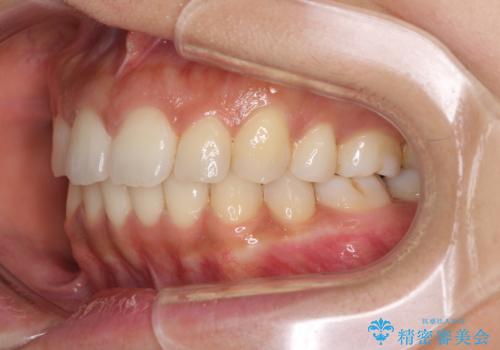

抜歯矯正の後戻り インビザラインによる再矯正治療

- 以前矯正治療をされていましたが、後戻りが起きたことを気にして来院された患者様です。

全顎的に認められた叢生を改善するため、インビザラインにて治療を行うこととしました。

前歯の叢生の改善を目的として、IPR(歯と歯の間を削る)と歯列全体の後方移動によって歯並びを整えることとしました。

毎日22時間の装着時間を守ってくださいましたが、ハイペースにマウスピースを交換することなく、慎重に治療を進めてくださったので、治療期間はやや長くなりました。

臼歯部も含め、叢生が綺麗に改善され、患者様には大変満足していただきました。